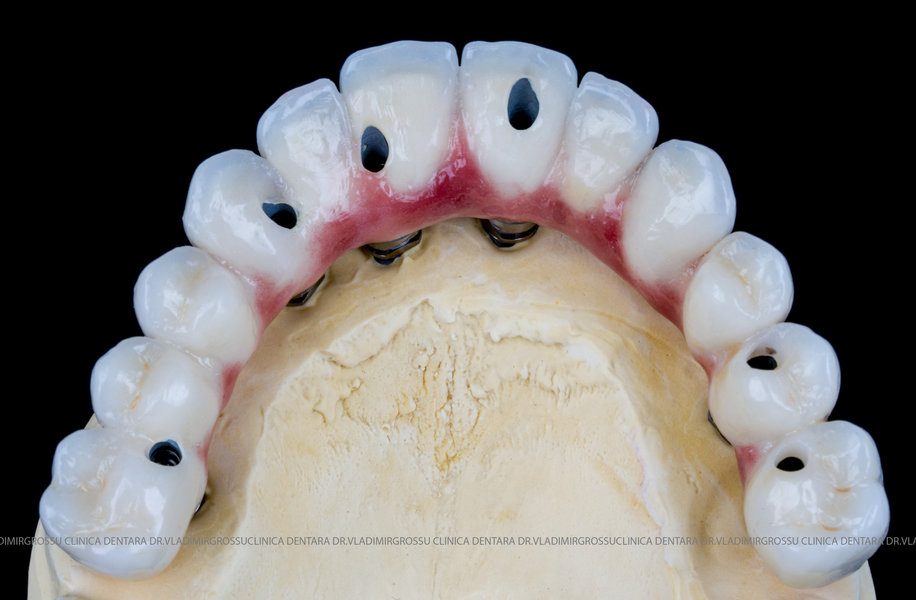

Cazuri clinice conceptul All-on-6